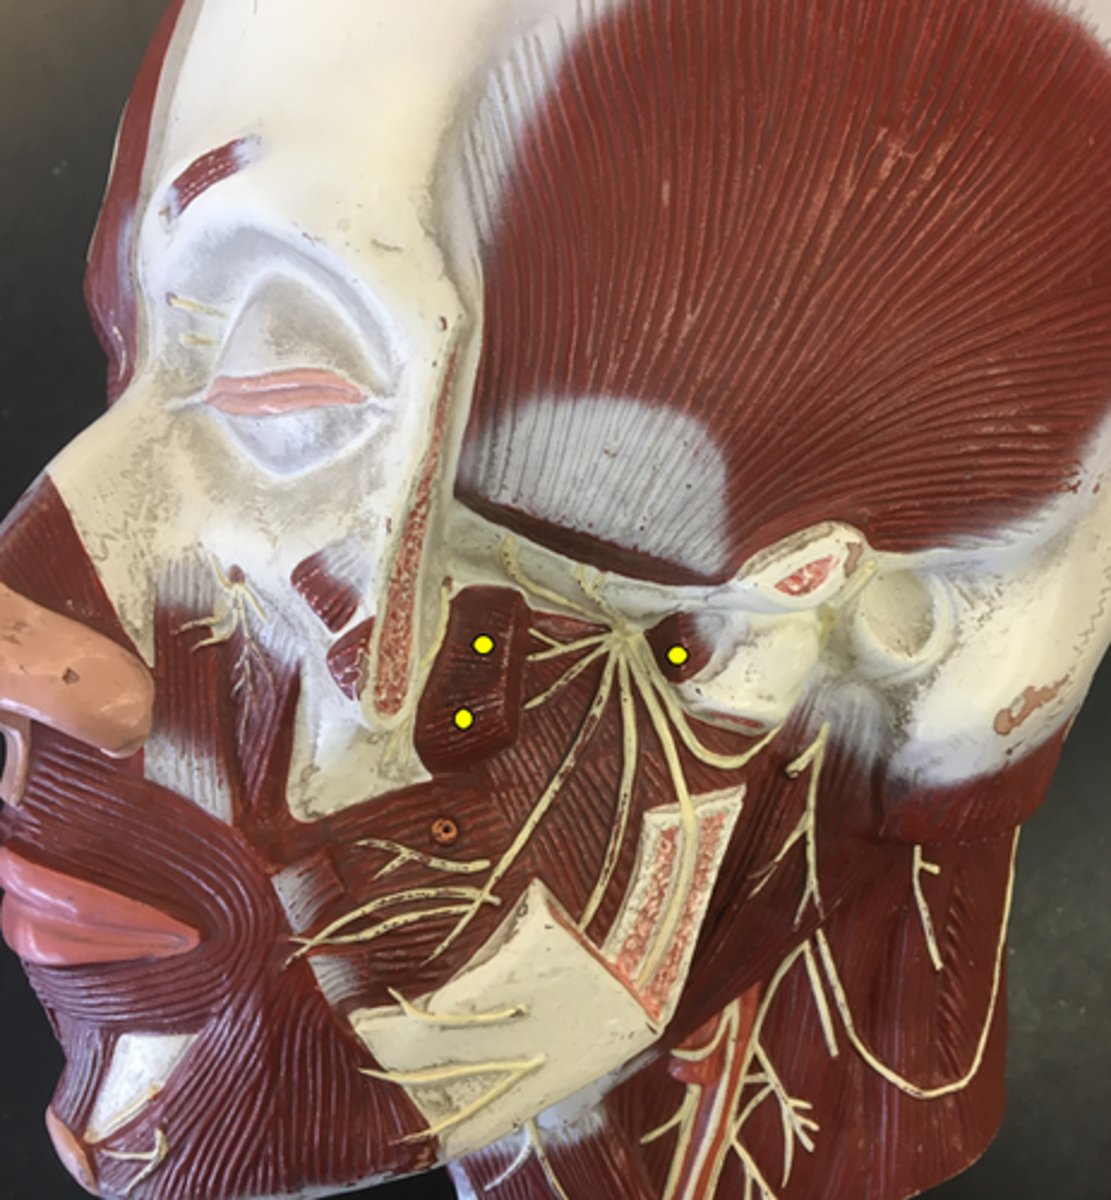

Zygomaticus Major

Zygomaticus Minor

Orbicularis Oris

Levator Labii Superioris

Depressor Anguli Oris

Depressor Labii Inferioris

Mentalis

Buccinator

Temporalis

Masseter